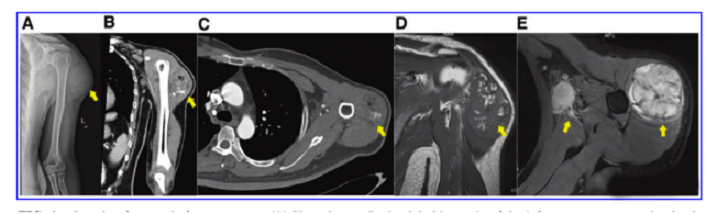

接受iPS細胞治療患者的畸胎瘤。(A) 在左上臂的三角肌中,觀察到一個圓形的混合密度腫塊,邊界不清,為9.6±5.2cm。(B) CT冠狀掃描顯示三角肌內(nèi)有一圓形混合密度腫塊,邊界不清。(C)增強CT軸向掃描顯示不均勻和中度強化。(D)MRI T1W以等信號為主,有不規(guī)則的高低信號區(qū)。(E) T2W也顯示高信號和斑片狀低信號區(qū),左腋窩有多個淋巴結(jié)腫大。

文中展示了該未成熟畸胎瘤的臨床,放射學和病理學特征,作者認為這種腫瘤不同于典型的未成熟畸胎瘤,特點是快速增長和局部淋巴結(jié)轉(zhuǎn)移,該新生腫瘤對典型化療方案沒有反應,磁共振成像顯示腫瘤的不均勻強化和豐富的血供。

組織病理學顯示未成熟的內(nèi)胚層、中胚層和外胚層組織由骨組織、軟骨組織、血管組織和腺樣組織組成,比典型畸胎瘤具有更多的細胞異型性。OCT4和SOX2的染色在腫瘤細胞中呈陽性,然而胰島細胞染色是陰性的,基因測序顯示了許多錯義突變,但沒有觀察到異常的基因重排、缺陷或拷貝數(shù)的變化。